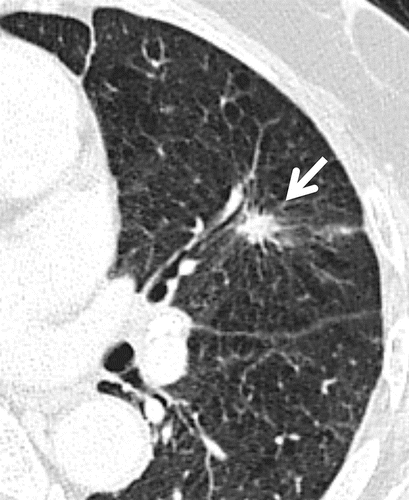

Спікулоподібні / шипоподбіні контури («промені»)

Утворення чи вузлики в легенях можуть мати гладку поверхню або нерівну поверхню через наявність шипів (виступів або гострих кінчиків) або лобулів (вигляд декількох округлих вузликів разом).

Однією з характерних ознак злоякісного процесу є спікулоподібні (шипоподбіні) контури. Це означає, що краї утворення виглядають нерівними і мають вигляд «променів», які розходяться в навколишню тканину. Такі контури можуть свідчити про інвазивний ріст пухлини та її проростання в навколишні тканини.

На відміну від доброякісних утворень, які часто мають чіткі й рівні межі, злоякісні зміни частіше виглядають «рваними» та неоднорідними.